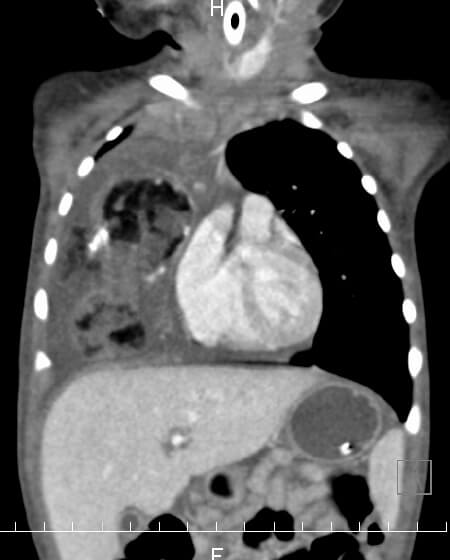

小児外科は心臓外科・脳外科・整形外科分野を除いた小児の一般外科であり、幅広い解剖学的知識が要求される診療科です。また、数100グラムの極低出生体重児から成人並の体重の中学生まで幅広い体格の子供を対象とするため、手術は繊細で正確な操作が要求される難しい科でもあります。当院においても既に、胸腔鏡下肺葉切除や胸腔鏡下縦隔腫瘍切除、腹腔鏡下後腹膜腫瘍切除、腹腔鏡下噴門形成、腹腔鏡下胆嚢摘出、腹腔鏡下先天性胆道拡張症手術、腹腔鏡下脾臓摘出、先天性食道閉鎖症や胎便性腹膜炎、小腸閉鎖症、横隔膜ヘルニア、鎖肛などの新生児手術、壊死性腸炎などの超低出生時体重児手術、胆道閉鎖症に対する葛西手術、ヒルシュスプルング病手術、肝芽腫や神経芽腫、横紋筋肉腫などの腫瘍全摘術、膵頭部腫瘍に対する膵頭十二指腸切除、正中頚嚢胞や側頚瘻などの頚部疾患手術、膵損傷治療など新生児から中学生までの高度な治療の実績が積まれています。